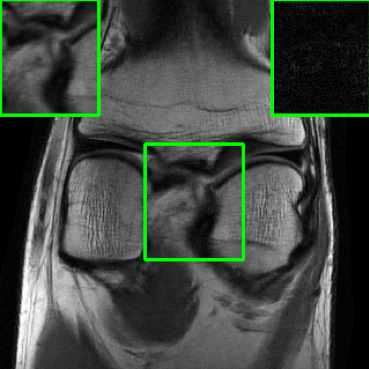

Figure 1 illustrates reconstructed images from the instabilities and the generalization challenges considered in this paper.

| PSNR = 30.8 dB | PSNR = 23.21 dB | PSNR = 22.18 dB |

| (a) | (b) | (c) |

| PSNR = 24.15 dB | PSNR = 27.26 dB |

| (d) | (e) |